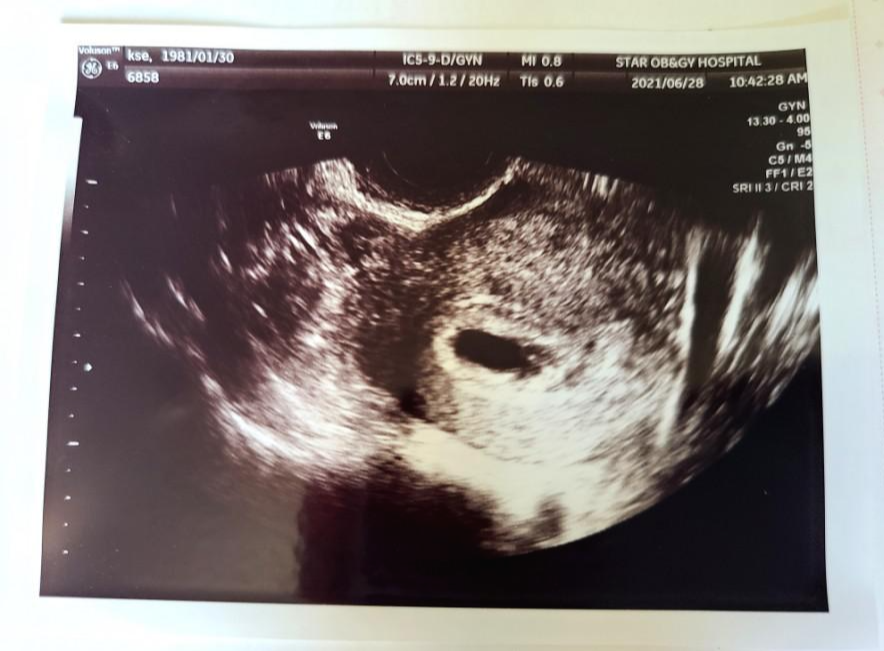

2021년 6월 28일은 제가 처음 우리 아기와 만난 날이에요.

이날은 의사선생님을 만나 초음파상으로 아기집과 난황을 확인했어요. 5주 차라고 하시더라구요.

제 배속에 이렇게 아기집이 있다는 게 신기하게 느껴졌어요.

아직 아기의 모습을 확인할 순 없었지만 테스트기가 아닌 의사선생님으로부터 임신을 축하한다는 말을 들으니 기분이 정말 묘하더라고요.